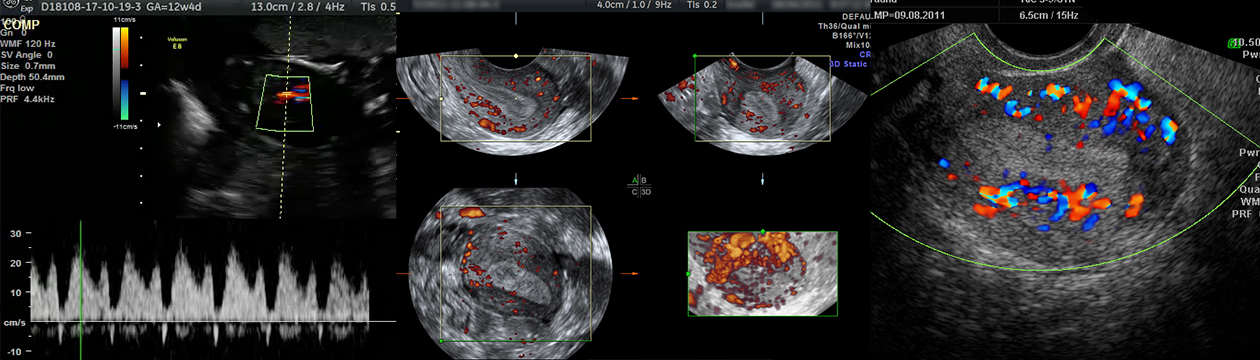

Kolor dopler ultrazvučni pregled (CD, PWD i pulsirajući dopler)

Ovaj ultrazvučni pregled podrazumijeva pregled prokrvljenosti genitalnih organa i male karlice pri čemu se ocjenjuje raspored krvnih sudova, te u njima mjeri otpor i brzina. S obzirom da se kretanje tečnosti u krvnim sudovima vidi u boji neki nazivaju ovaj pregled i ULTRAZVUK U BOJI.

Ova vrsta ultrazvučnih pregleda od posebnog je značaja kod mioma materice i cisti na jajnicima s obzirom da je to jedan od načina pouzdane procjene o mogućnosti rasta pomenutih tumora ali i otklanjanje ili potvrđivanje sumnje da se radi o malignom tumoru. Ovi pregledi traju duže, i do 30 minuta a mogu se obavljati vaginalnim putem ili preko stomaka (abdominalno).

Ova vrsta ultrazvučnog pregleda je od posebne važnosti kod krvarenja u malim trudnoćama jer pouzdano i brzo može dati ocjenu o vitalnosti ploda od koje zavisi prognoza.

Svi pregledi se rade na ultrazvučnim aparatima Voluson E-8 expert!